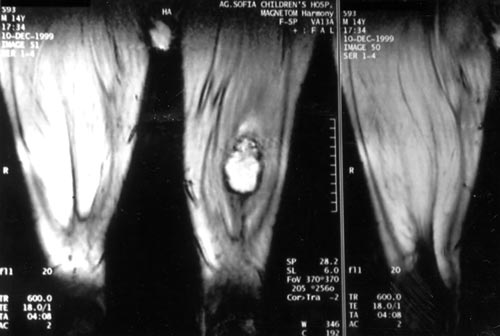

κλινική βελτίωση, η πάσχουσα περιοχή ελέγχθηκε με MRI. Διαπιστώθηκε σχηματισμός

αιμορραγικής κύστης εντός του αριστερού τετρακέφαλου μυός με τη μορφή ψευδοόγκου

(εικόνα 2).